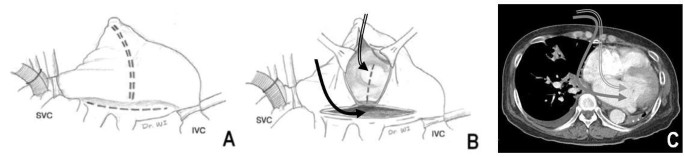

During the surgery, we cannulated the right femoral artery and vein. Median sternotomy revealed that the right lung was crossing the midline, while the heart was markedly displaced and rotated into the left hemithorax. Supplementalrily we directly cannulated the superior vena cava and performed a cardiopulmonary bypass (CPB). During the CPB, we used aggressive intraoperative ultrafiltration to both reduce lung water content and pulmonary vascular resistance. After antegrade cardioplegia delivery without topical cooling, the right atrium was incised from the tip of the appendage to the mid-portion of the interatrial groove. Additionally, a left atrial incision was made parallel to the interatrial groove and connected to the right atrial incision. The additional incision was made across the interatrial septum to the fossa ovalis to grant the surgeon better visibility of the mitral valve and to facilitate the valve’s exposure (Figure 3). We inspected the mitral annular dilatation and the prolapsed A2 portion with degenerative change; this examination revealed that the tricuspid annulus was markedly dilated. We then performed a modified Cox-Maze III procedure using cryoablation. Thereafter, 5/0 Prolene sutures were employed to perform an Alfieri stitch repair of the mitral cusp. The mitral annulus was stabilized with a Cosgrove-Edwards ring, and tricuspid annuloplasty was performed with an Edwards MC3 ring. CPB was discontinued without any difficulty. Total bypass time was 209 min and aortic cross clamp time was 173 min.

Modified incisions used during the patient’s surgery. (B) An additional septal incision can facilitate exposure of the mitral valve. (B, C) A left atrial incision (solid arrow) would not provide as much visibility of the mitral valve as the modified septal incision (double arrow). Thus, the latter was used to maximize the surgeon’s view during the procedure. These incisions also were used for the modified Cox-Maze III operation. IVC: inferior vena cava; SVC: superior vena cava.

An autopneumonectomized lung can displace and rotate the heart into the ipsilateral hemithorax, thereby making exposure cumbersome through the conventional approach. As a result, it may be preferable to use an alternative surgical approach after pneumonectomy [5]. However, it is also feasible to perform median sternotomy, which is a more familiar way to conduct cardiac surgery after pneumonectomy [1, 2, 6]; we decided to perform a median sternotomy with femoral cannulations. We hoped that the use of a median sternotomy with peripheral cannulations would prevent the surgical field from becoming crowded with cannulae; additionally, we anticipated it would improve exposure, since a large number of cannulae and surgical instruments in the operative field would limit a surgeon’s vision from the right side when the heart is severely rotated into the left side. A modified septal incision combined with biatrial incisions also seemed likely to facilitate exposure of the mitral valve, since the left atrial structures were located farther far away from the surgeon’s vision than those on the right (Figure 3).